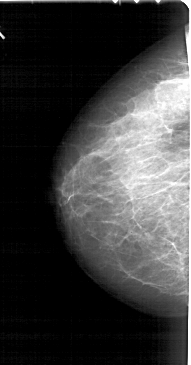

A_1794_1.LEFT_MLO

LEFT_MLO LINES 5491 PIXELS_PER_LINE 2746 BITS_PER_PIXEL 12 RESOLUTION 43.5 NON_OVERLAY